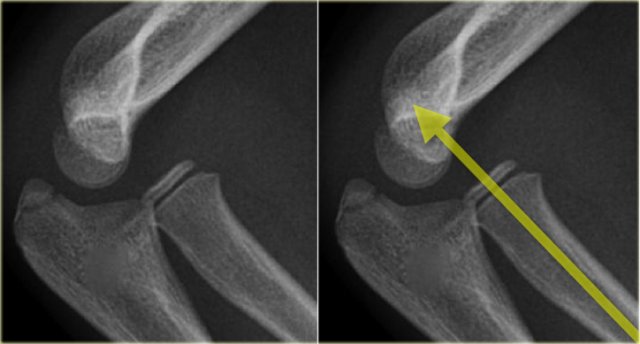

Radiocapitellar line

A line drawn through the centre of the radial neck should pass throught the centre of the capitellum, whatever the positioning of the patient, since the radius articulates with the capitellum (figure).

In dislocation of the radius this line will not pass through the centre of the capitellum.

On the left we see, that the radiocapitellar line goes through centre of the capitellum on every radiogragh even though C and D are not well positioned.

Notice supracondylar fracture in B.

On the left more examples of the radiocapitellar line.

The right lower image shows an obvious dislocation of the radius.